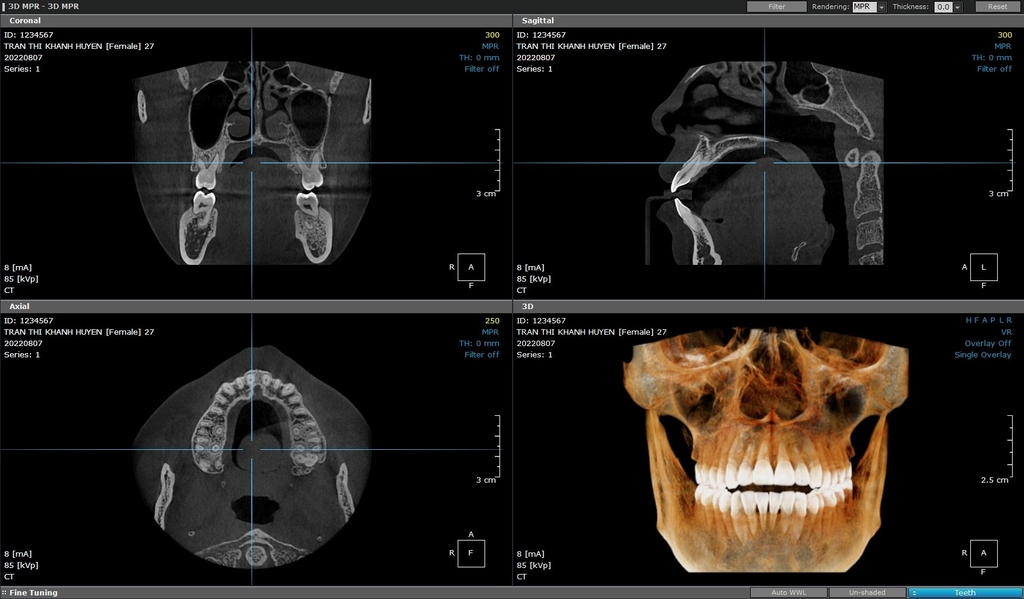

Cone Beam CT (Cone Beam Computed Tomography) là máy chụp phim thông qua sự kết nối giữa máy tính và các phần mềm chuyên dụng để xuất ra hình ảnh 3 chiều của mô răng, mô mềm, xương hàm và ống thần kinh chỉ bằng 1 lần quét duy nhất. Hình ảnh thu được giúp các nha sĩ có được phác đồ chi tiết, để lên kế hoạch điều trị đúng và tốt nhất cho người bệnh.

Chụp Cone Beam CT hay còn gọi chụp cắt lớp hình nón, là một loại Chụp phim Cone Beam CT là một kỹ thuật hình ảnh y khoa hiện đại sử dụng tia X để tạo ra những hình ảnh 3D chi tiết về hàm răng, xương hàm và các cấu trúc xung quanh. Khác với phim X-quang 2D truyền thống chỉ cung cấp một hình ảnh phẳng, Cone Beam CT cho phép nha sĩ quan sát toàn bộ hàm răng từ nhiều góc độ khác nhau, giống như một bản đồ 3D của vùng miệng.

1. Ưu điểm của Cone Beam CT

• Hình ảnh 3D chi tiết: CBCT tạo ra hình ảnh ba chiều rõ nét về cấu trúc xương hàm, răng, mô mềm và thần kinh. Điều này giúp bác sĩ nha khoa đánh giá toàn diện tình trạng răng miệng của bệnh nhân, từ đó đưa ra kế hoạch điều trị phù hợp.

• Chẩn đoán chính xác các bệnh lý: CBCT giúp phát hiện sớm các bệnh lý về răng miệng như u nang, khối u, viêm nhiễm, các vấn đề về xương hàm... mà các phương pháp chụp Xquang 2D khó phát hiện.

• Lập kế hoạch điều trị chính xác: Hình ảnh 3D chi tiết từ CBCT giúp bác sĩ lập kế hoạch điều trị một cách tỉ mỉ và chính xác hơn.

• Giảm thiểu rủi ro trong phẫu thuật: Nhờ hình ảnh 3D, bác sĩ có thể xác định chính xác vị trí của các cấu trúc giải phẫu, giúp giảm thiểu tối đa các biến chứng trong quá trình phẫu thuật.